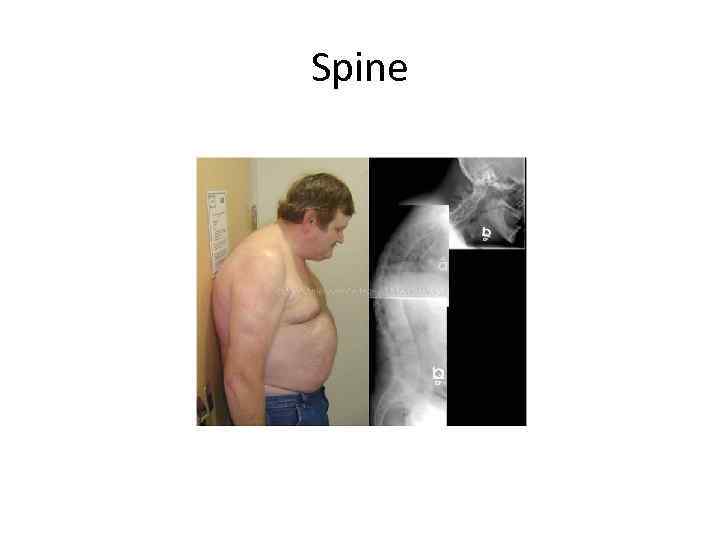

Spine